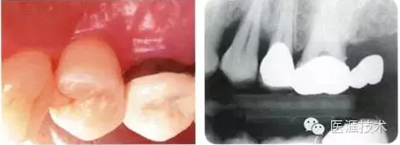

初期治療后左上4的近中有牙槽骨吸收三角區(qū)的凹凸,目前堅(jiān)持進(jìn)行維護(hù)的狀態(tài)下牙周袋深度仍有6mm。菌斑控制做得很好,牙齦組織緊繃健康,沒有出血現(xiàn)象。